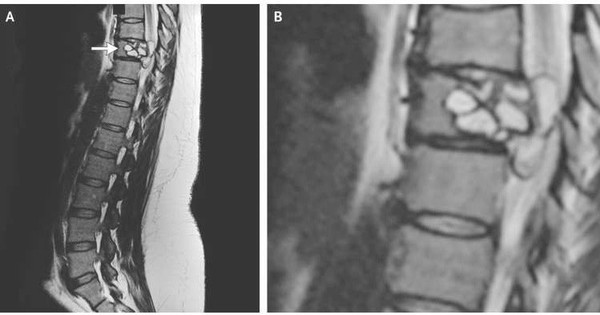

Các bác sĩ sau đó quyết định chụp cộng hưởng từ, và thấy được một phần của câu chuyện. Trong bản báo cáo được công bố trên tạp chí Medicine, thì tại đốt sống ngực số 9 của người phụ nữ này có một khối u, và nó khiến cho xung động thần kinh truyền xuống chân gặp rất nhiều cản trở.

Phương án điều trị nhanh chóng được quyết định: người phụ nữ được phẫu thuật loại bỏ khối u, sau đó cấy một đốt sống nhân tạo vào đó. Tuy nhiên ngay tại bước này, mọi vấn đề đã được sáng tỏ, và nó khiến rất nhiều người phải rùng mình.